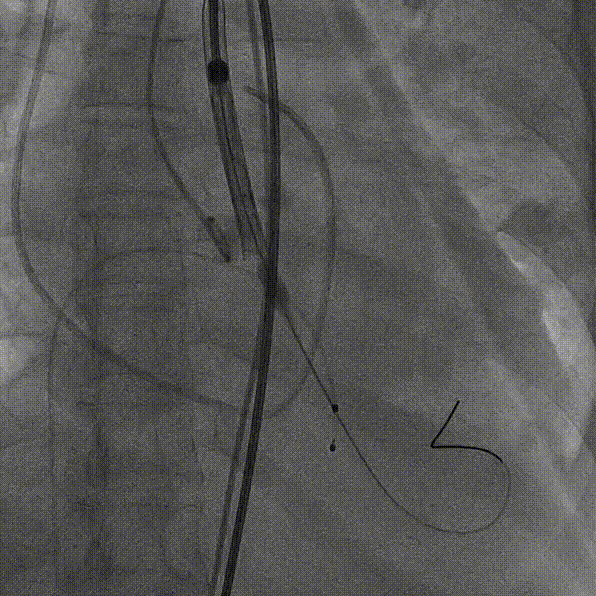

3.TaurusElite AV26号瓣膜定位及释放。瓣膜初始定位瓣下2mm,开花后120次起搏,释放到工作位后造影显示锚定充足,位置良好,冠脉未见遮挡,继续缓慢旋转手柄,瓣膜逐一脱钩,顺利释放。

瓣膜初始定位

瓣膜释放过程

瓣膜脱钩